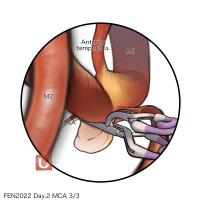

FEN2022シリーズ